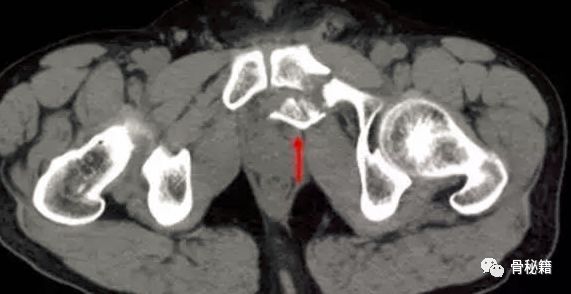

行CT,发现腹腔有10*10*15的血肿位于耻骨骨折旁边。

行血管造影后确定了为死亡之冠出血,后行血管栓塞闭孔动脉后,出血停止。一周后康复出院。